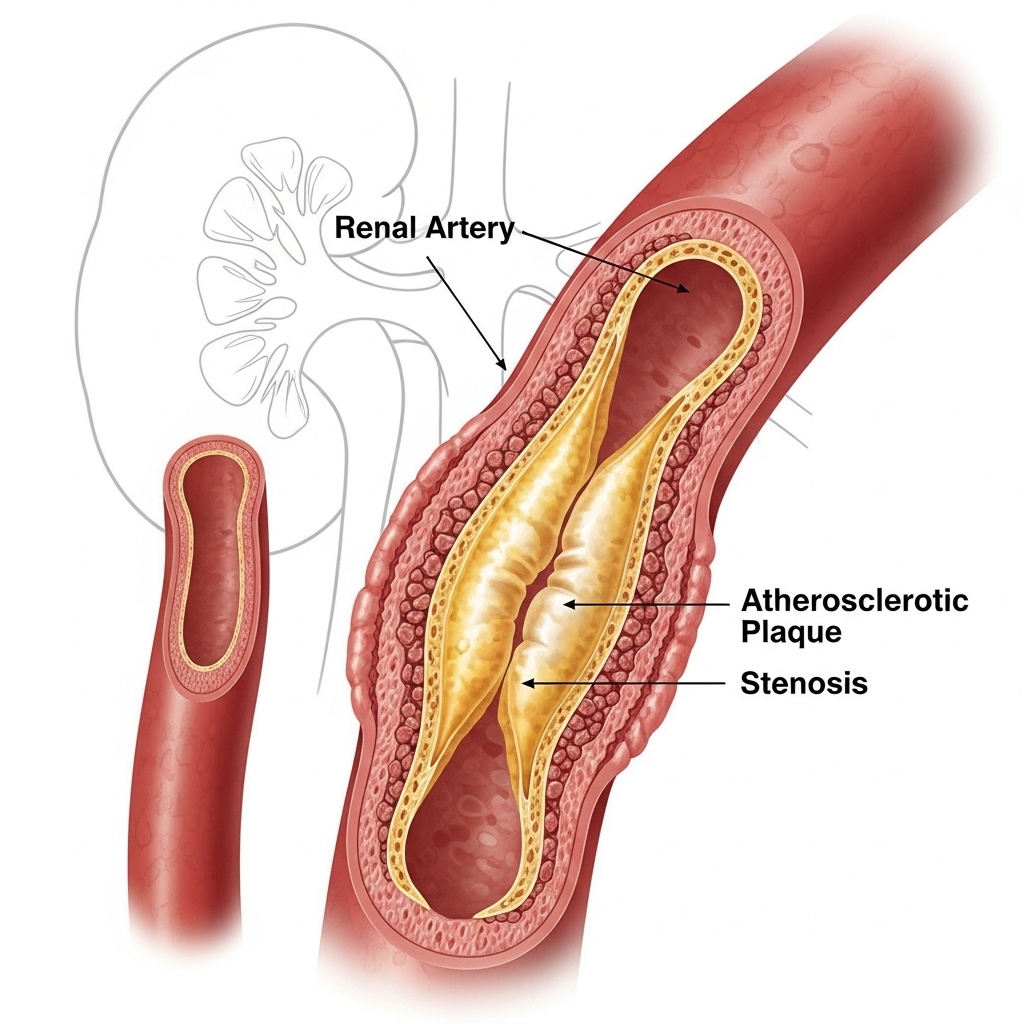

Renal artery stenosis (RAS) is a condition where the arteries that supply blood to your kidneys become narrowed or blocked. This kidney artery narrowing reduces blood flow to the kidneys, leading to high blood pressure and potentially serious complications if left untreated. Understanding this condition is the first step toward effective management and recovery.

Several factors can contribute to the development of renal artery stenosis:

Detailed imaging that provides clear pictures of the renal arteries and any narrowing.

The gold standard for diagnosing renal artery stenosis with precise visualization.